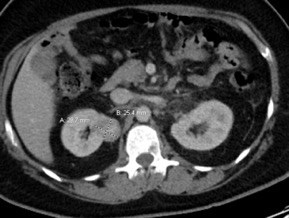

Case Presentation: A 40-year-old male presented to the emergency department with complaints of back pain for 3 weeks. He described the pain as aching and circumferential involving the sternum, right ribs, shoulders, and back. His previous medical history was unremarkable and he never had any prior imaging studies. Plain radiographs of the spine did not show any osseous abnormalities. Because of the patient’s highly elevated alkaline phosphatase (1,051 IU/L), a computed tomography (CT) scan of the chest, abdomen, and pelvis was performed (figure 1). This revealed an enhancing right upper pole renal mass suspicious for renal cell carcinoma with nodal, left adrenal and extensive bony metastasis. In the chest, there were extensive lytic and sclerotic bone metastases. Interventional Radiology performed a CT guided core biopsy of one of the metastatic lesions in the left iliac crest; cytology reported metastatic malignant cells with immunohistochemical findings positive for Ae1/Ae3 and PAX8. This was highly suggestive of metastatic renal cell carcinoma, however, the specific histological subtype (clear cell vs non-clear cell) was not identified due to an insufficient tissue sample from the earlier core biopsy. A subsequent positron emission tomography (PET) scan revealed extensive metastases with multiple soft tissue implants, retroperitoneal lymph nodes and extensive osseous involvement (figure 2). The patient was scheduled for a repeat core biopsy (retroperitoneal) for a more specific histological diagnosis (clear cell vs non-clear cell) on the demand of the treating oncologist and commenced on treatment with Sunitinib in the interim.